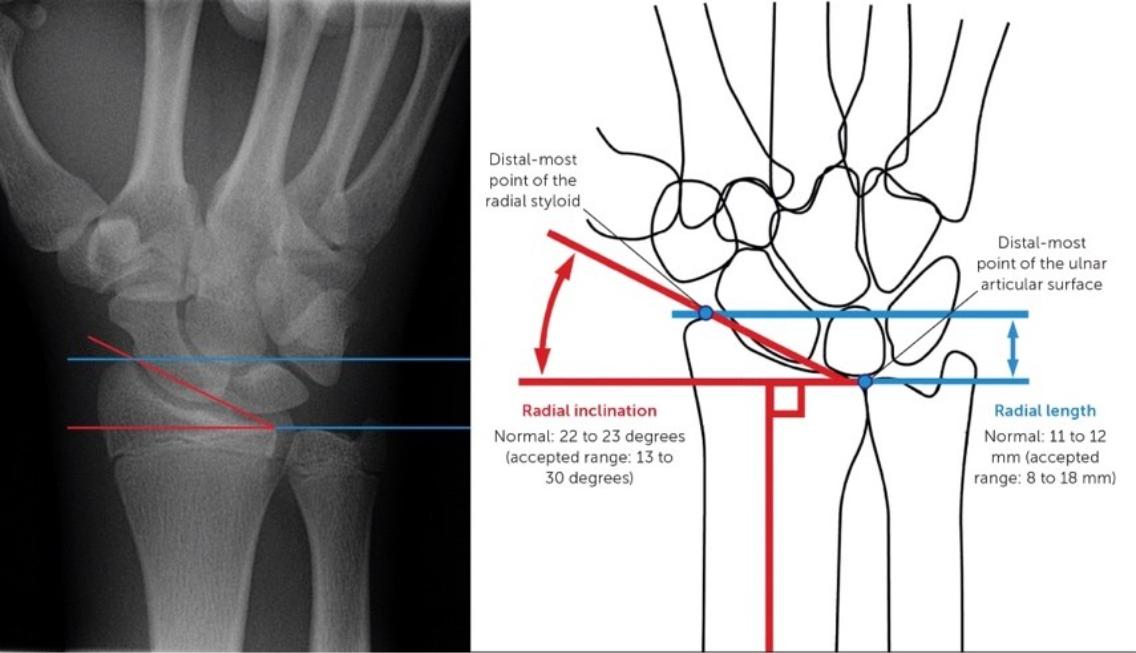

目前標準手術方式為使用「互鎖式鈦合金鋼板」固定,不僅減少螺絲鬆脫風險,對骨質疏鬆者尤其有利,還可縮短固定時間,加快進入復健期,避免關節僵硬。

若骨折未癒合或癒合不良,常出現橈尺骨長短不一的問題,處理方式有兩種:縮短尺骨(常用)與延長橈骨(較困難),進行骨重建時,可能需搭配人工骨移植,提高癒合成功率,類似植牙前強化骨床的概念。